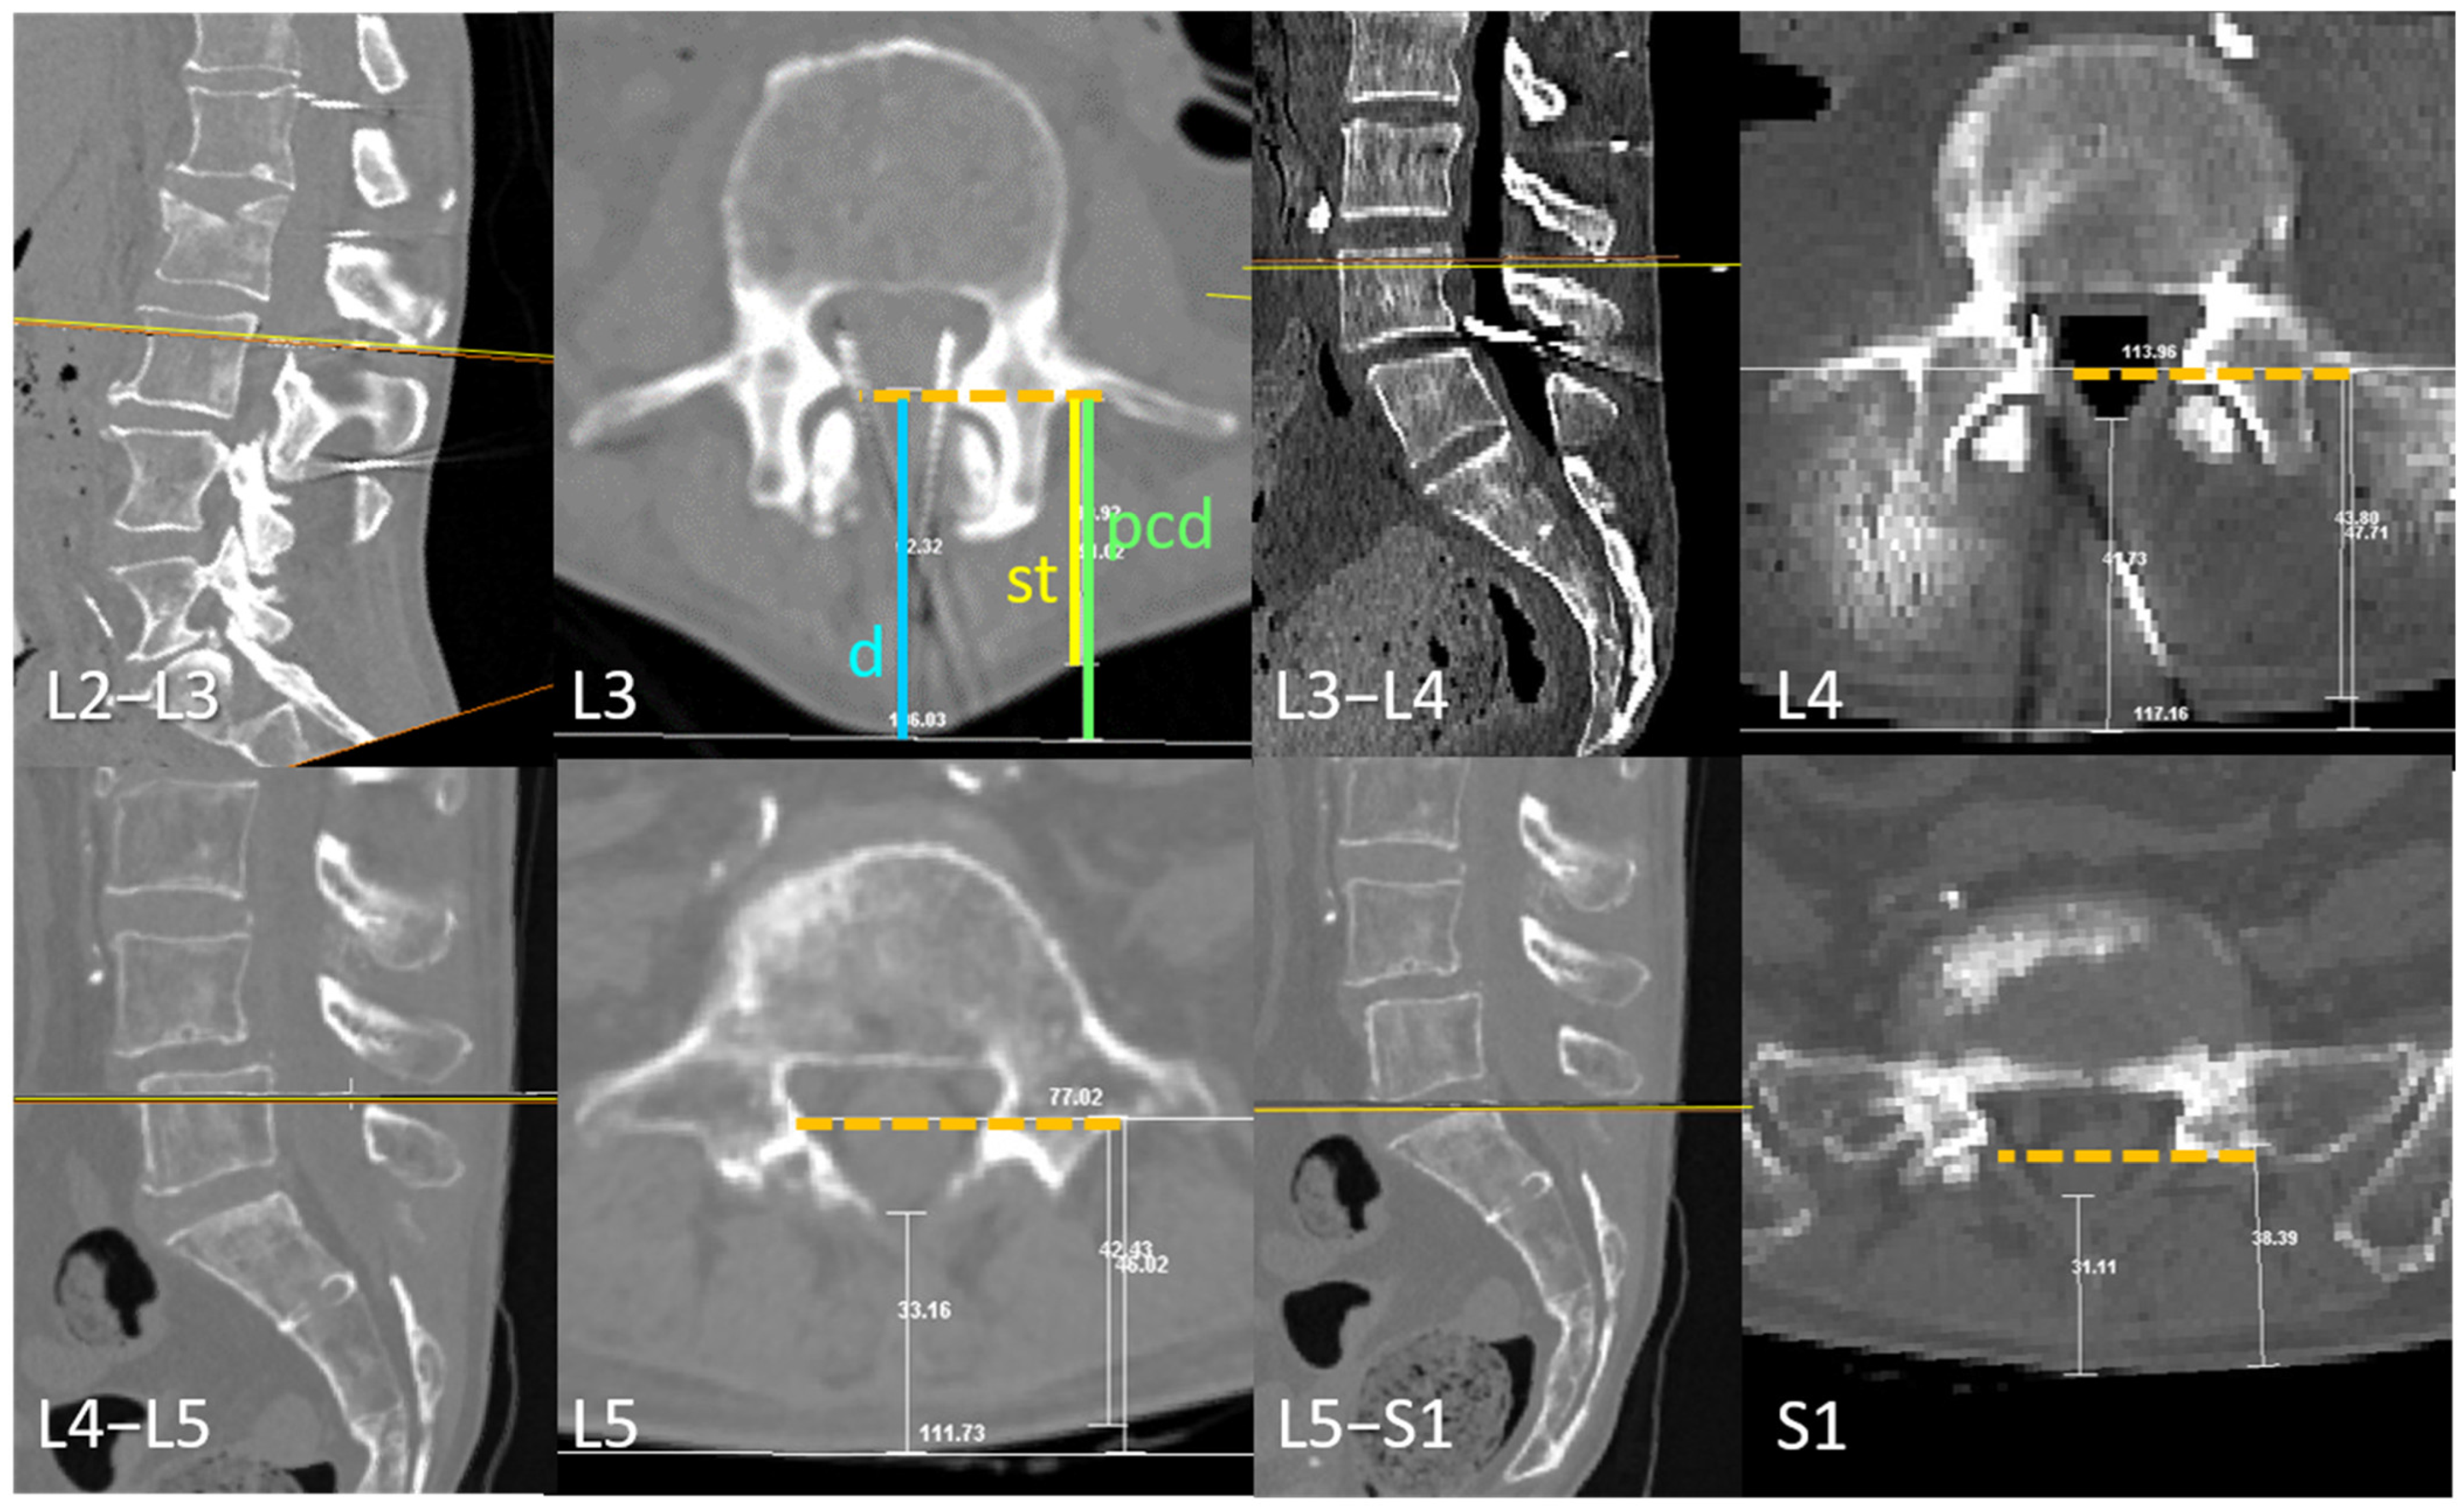

2.1.1. Transverse Process and Dural Sac Alignment

3.1. Transverse Process and Depth Level Within the Dural Sac

3.2. D Reconstruction, Transverse Process and Interlaminar Window